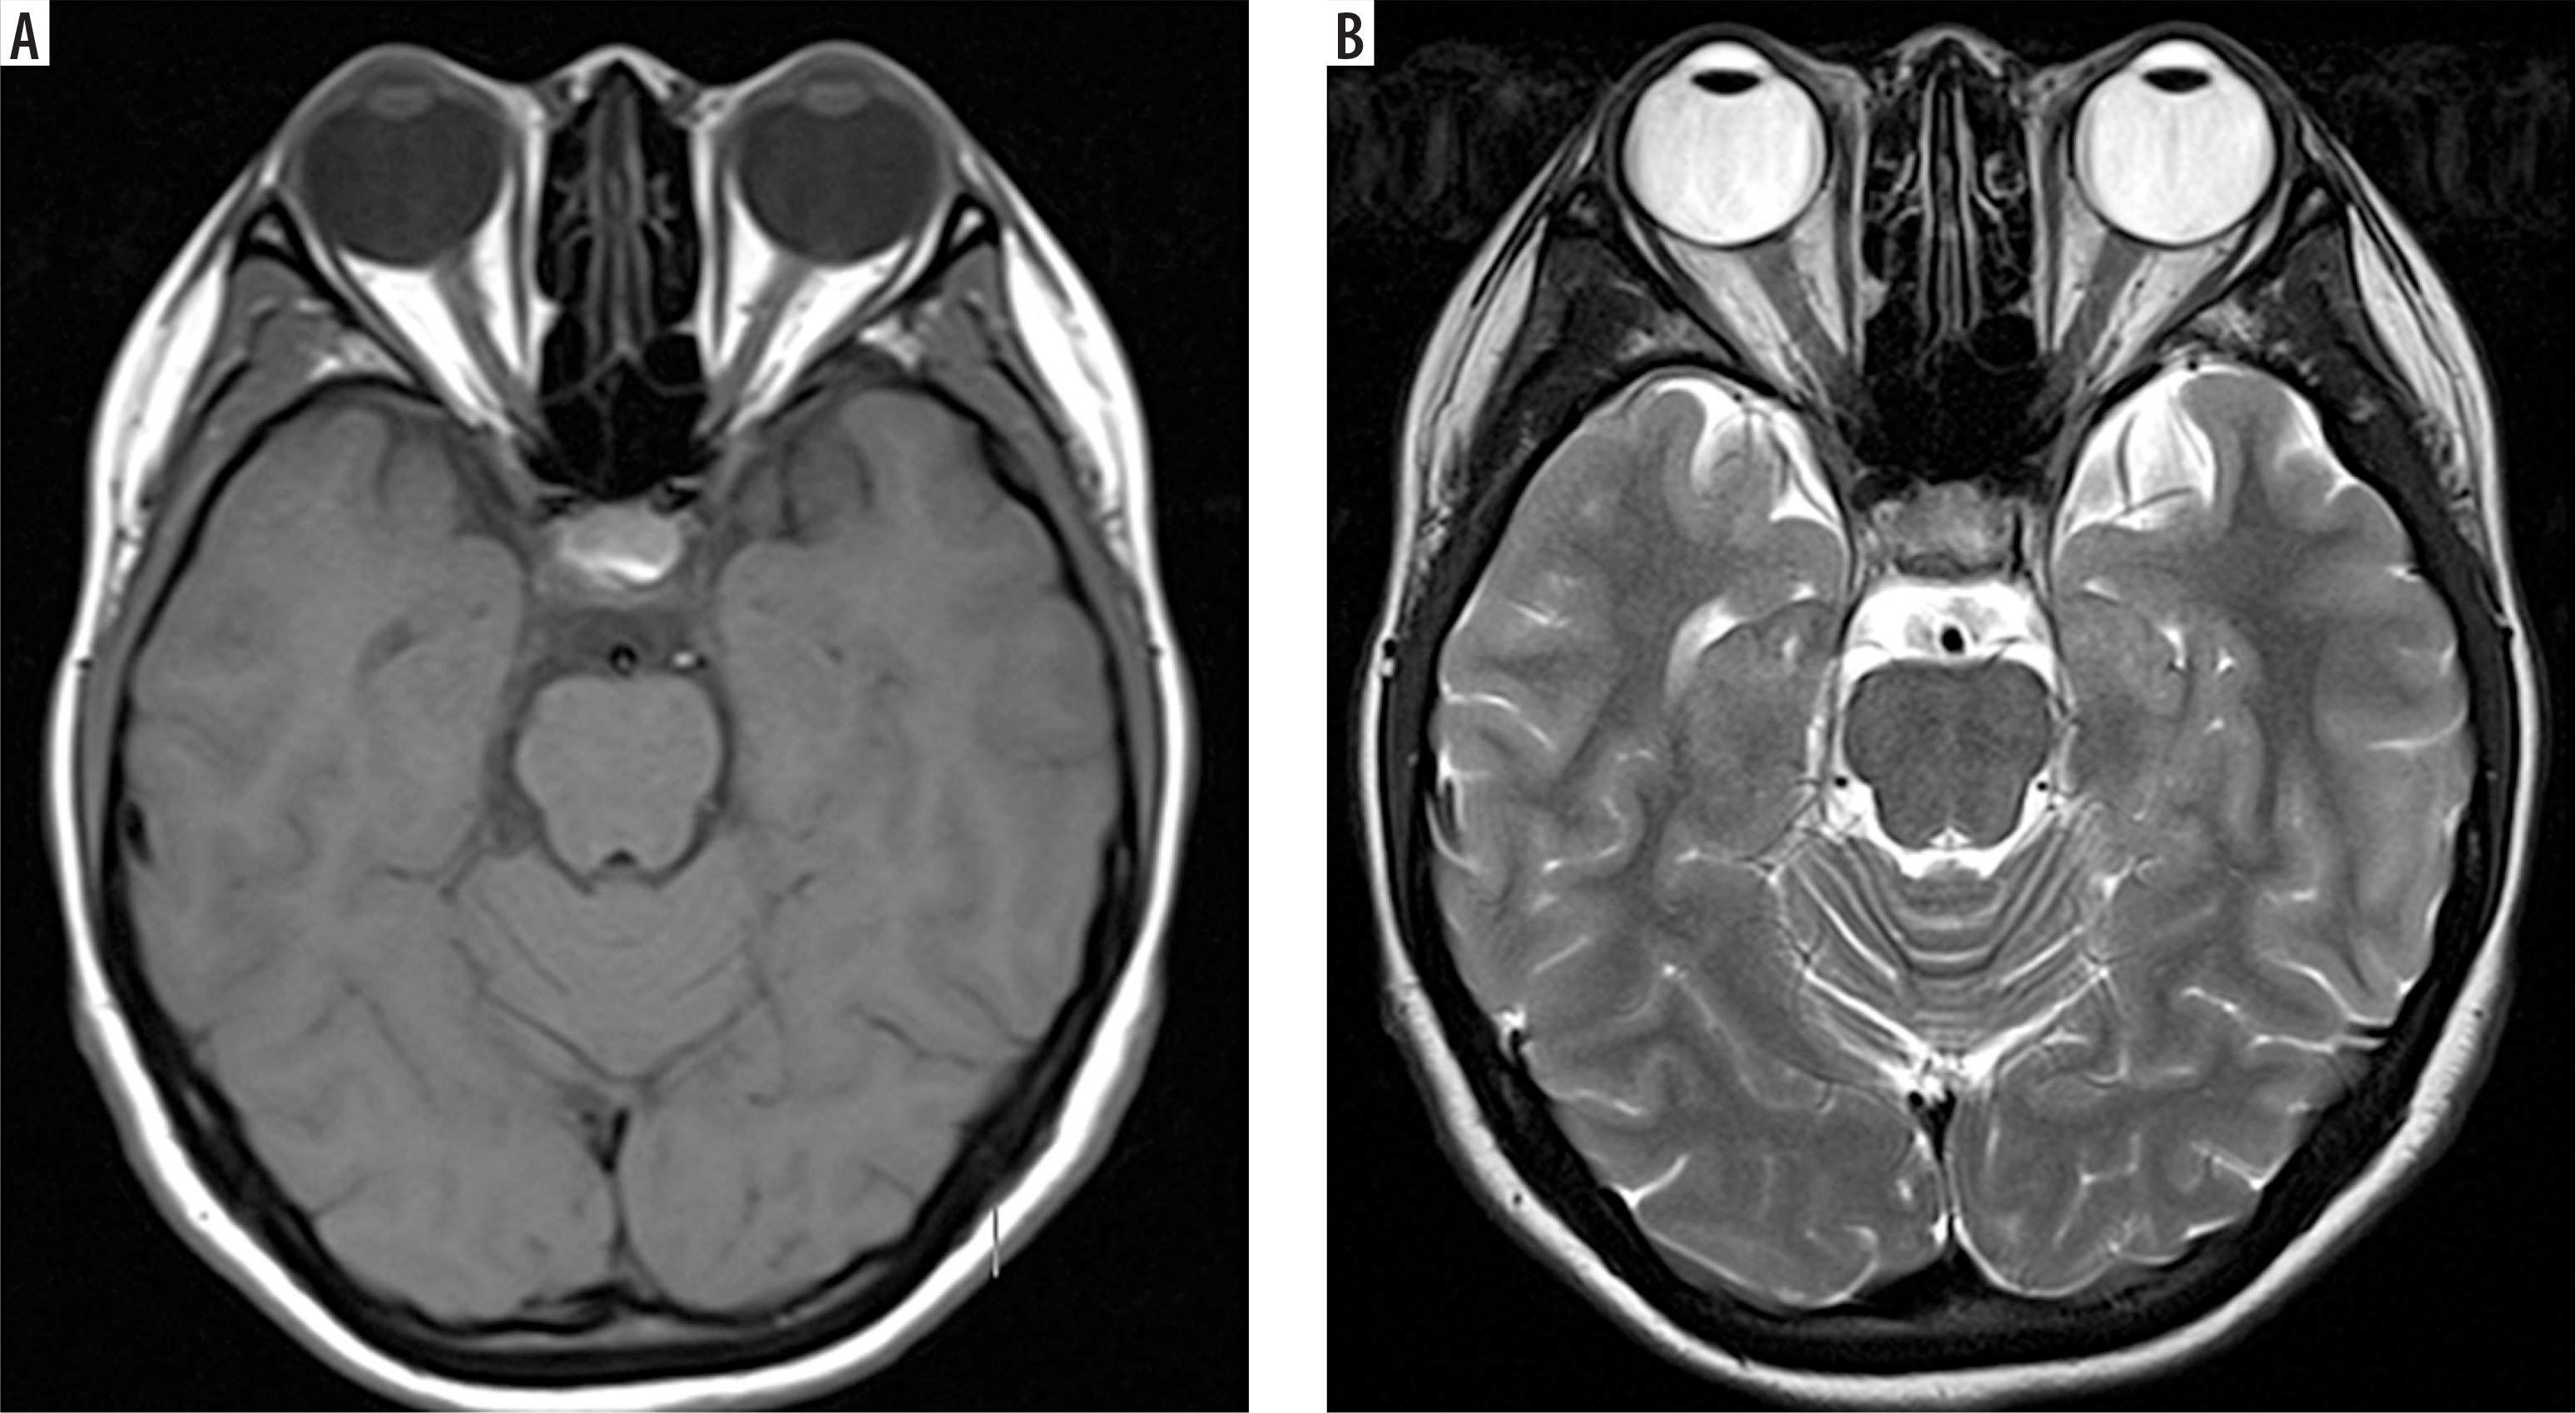

Understanding these differences helps in interpreting MRI images. In T1-weighted sequences, cerebrospinal fluid (CSF) and vitreous humour are hypointense, fat is hyperintense, muscle appears grey, and brain white matter appears brighter than grey matter. In contrast, T2-weighted sequences show CSF and vitreous humour as hyperintense, fat as white, muscle as grey, grey matter as grey, and white matter as hypointense [19,20] (Figure 2).

Figure 2

Axial section of normal brain MRI. A) T1-weighted MRI image – note how CSF and vitreous humour appear dark. B) T2-weighted MRI image – note how CSF and vitreous humour are bright. Recognising these normal signal intensities is essential for accurately identifying pathological changes or surgical planning [Courtesy: Radiopaedia. DOI: https://doi.org/10.53347/rID-153576, rID: 153576]